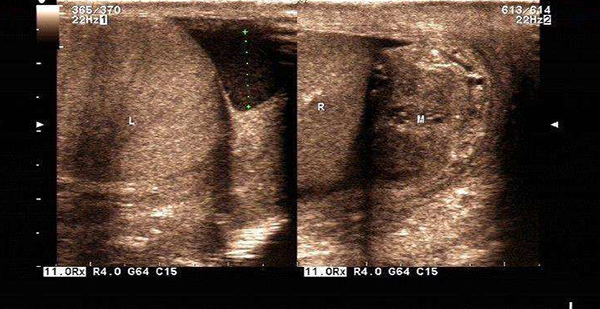

B超检查出双侧附睾尾部梗阻

医生让唐先生考虑手术治疗,唐先生考虑了很久,最终同意了手术治疗,之后便就医进行了双侧输精管附睾管吻合术、双侧附睾穿刺术, 手术过程很顺利,术后一直服用中西医药物调理,并且术后恢复情况良好。